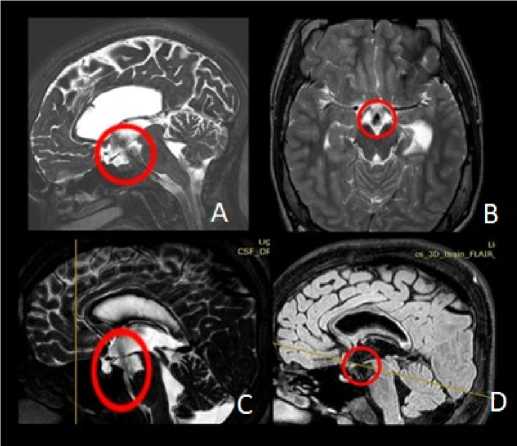

Контрольное магнитно-резонансное исследование головного мозга с ликвородинамической пробой выполнялось через 1, 3 и 6 месяцев после оперативного вмешательства. Примеры контрольных МРТ-исследований после эндоскопической вентрикулоцистерностомии представлены на рис. 5. В ходе обследования оценивались размеры желудочковой системы и наличие ликворотока через сформированную вентрикулостому на дне III желудочка. Клиническая оценка включала анализ выраженности признаков гипертензионно-гидроцефального синдрома. Всем пациентам проводился осмотр офтальмолога с оценкой состояния глазного дна и дисков зрительных нервов.

Рисунок 5. Контрольное МРТ-исследование головного мозга после эндоскопической вентрикулоцистерностомии III желудочка. Красным цветом обозначены сформированные стомы дна третьего желудочка